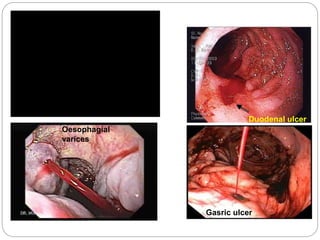

Duodenal ulcer

Gasric ulcer

Oesophagial

varices